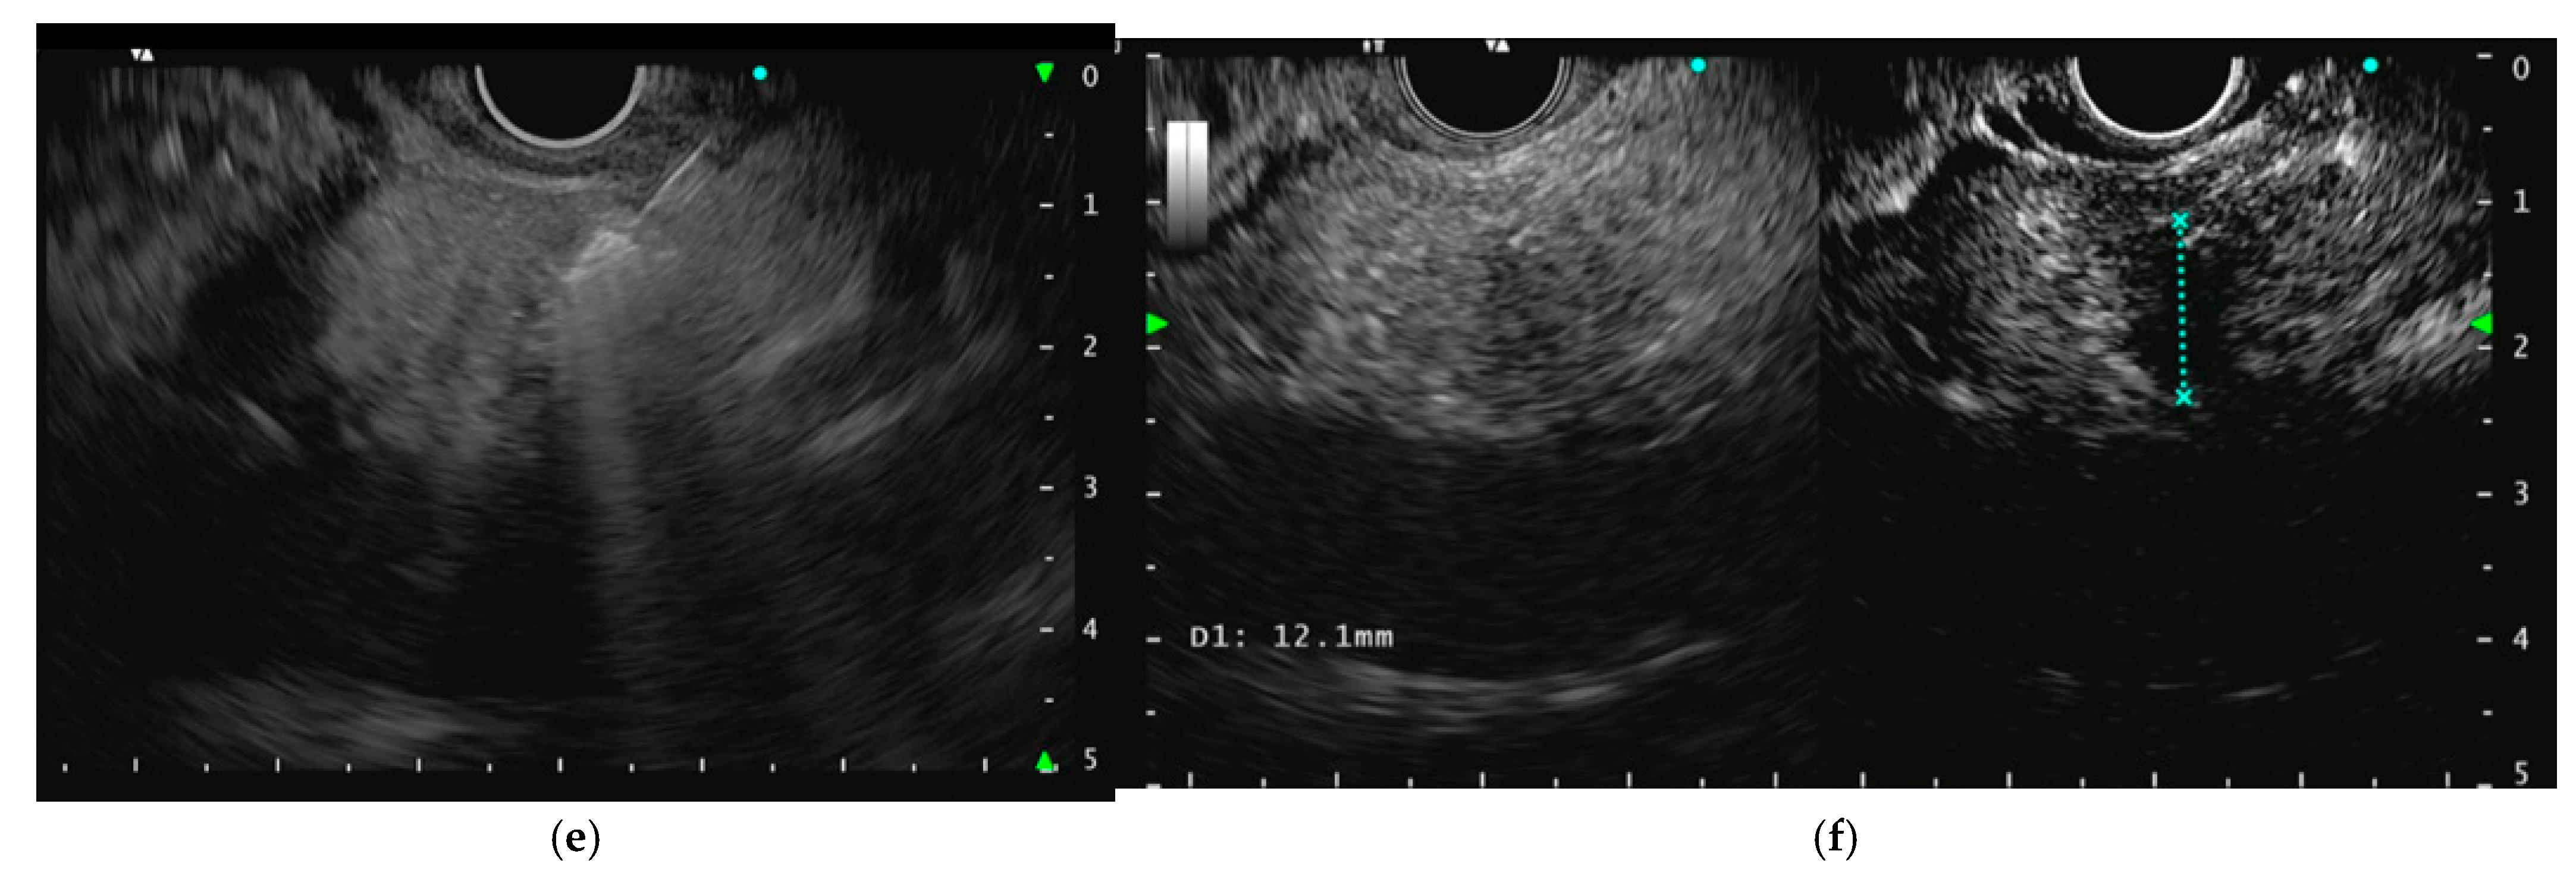

3.1. Procedure

- Choi, J.H.; Seo, D.W.; Song, T.J.; Park, D.H.; Lee, S.S.; Lee, S.K.; Kim, M.H. Utility of Contrast-Enhanced Harmonic Endoscopic Ultrasound for the Guidance and Monitoring of Endoscopic Radiofrequency Ablation. Gut Liver 2020, 14, 826–832. [Google Scholar] [CrossRef] [PubMed]